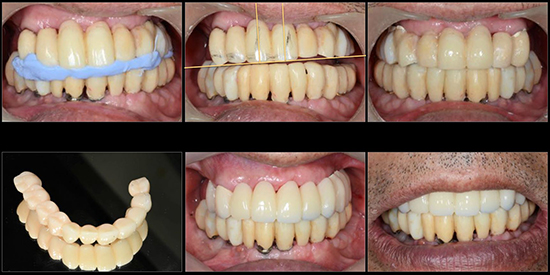

治療後01

治療後02

治療後03

治療後04